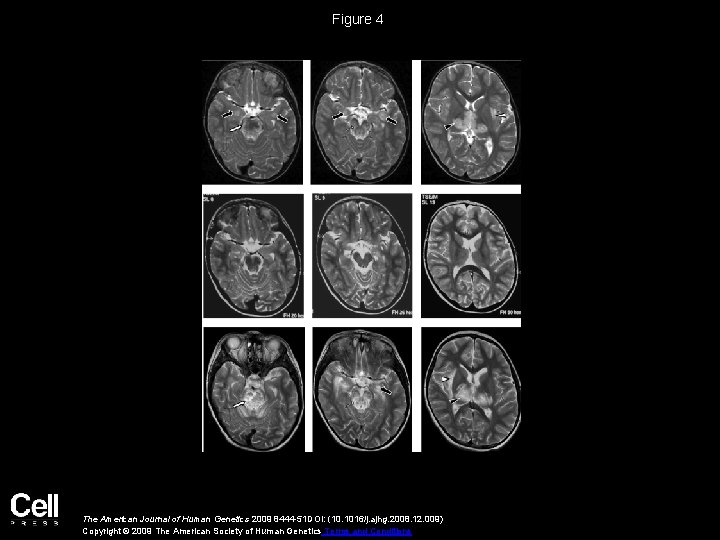

Figure 4 The American Journal of Human Genetics 2009 8444 -51 DOI: (10. 1016/j.

Figure 4 The American Journal of Human Genetics 2009 8444 -51 DOI: (10. 1016/j. ajhg. 2008. 12. 009) Copyright © 2009 The American Society of Human Genetics Terms and Conditions